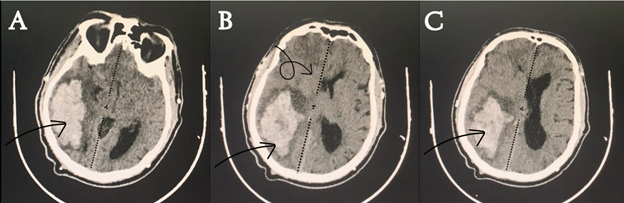

Following the successful evacuation of the intraparenchymal hematoma and the alleviation of elevated intracranial pressure, a Postoperative non-contrast brain CT scan showed significant improvement and no residual hemorrhage or pressure effect could be seen (Figure 2). An important aspect of the procedure involved the thoughtful repositioning of the previously removed bone flap. This restorative step was undertaken with extreme precision, considering both structural integrity and the capacity for physiological expansion within the cranial vault. The bone flap was carefully secured in a manner that not only provided protection to the vital neural structures beneath but also allowed for the accommodation of normal physiological processes and fluctuations within the intracranial environment. The surgery went smoothly, even though the bone flap moved because of the ongoing high pressure inside the skull.

Figure 2 Postoperative non-contrast brain CT scan showing the region where the previous hemorrhage occurred, with a noticeable return to the normal midline position of brain structures. (A) Lower brain section CT scan with notable return to midline (dashed line), and a clearly seen bone flap (orange curved arrow). (B) Upper brain section CT scan showing normal position f midline structures.